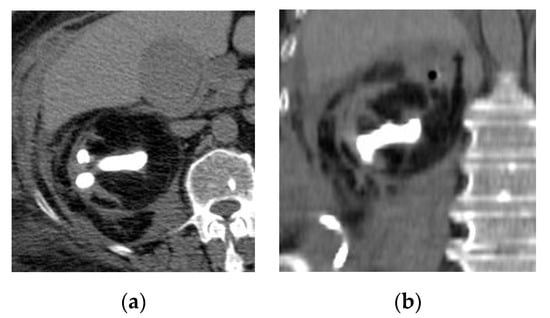

2.6. Emphysematous Urinary Tract Infection

| Emphysematous UTIs | Gas in the renal parenchyma, collecting system, bladder lumen and sometimes in the perirenal and perivesical tissue. |